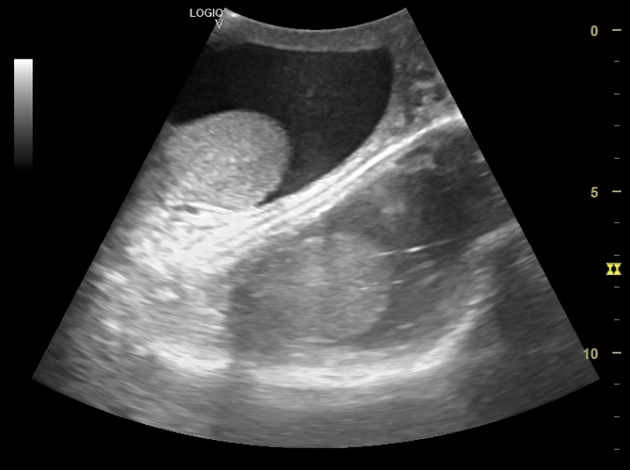

Echogenicity- Hypoechoic

echo poor, dark grey

less dense soft tissue